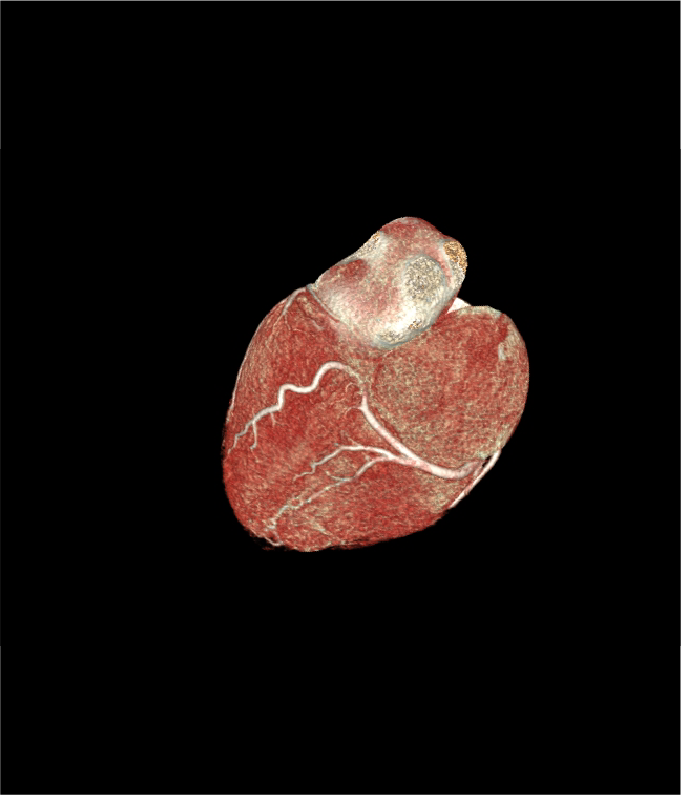

Tomografía cardiaca

Este estudio es adquirido con un tomógrafo de alta velocidad y baja radiación que permite evaluar las arterias coronarias y demostrar la ausencia o la presencia de placas ateromatosas, que son las que ocasionan un infarto (enfermedad arterial coronaria). Mediante la emisión de rayos X es posible obtener imágenes bidimensionales y tridimensionales del exterior y del interior de las arterias coronarias, del corazón y de la función cardiaca.

Cuando es necesario hacer una evaluación mas precisa de tus arterias coronarias la tomografía cardiaca permite, mediante la inyección de contraste por una vena del brazo, estudiar el interior de las arterias y demostrar si existen o no placas que impiden el paso de sangre hacia el corazón, a esta modalidad de la tomografía cardiaca le conocemos como angiotomografía coronaria, que se adquiere en 30 a 60 minutos, y es hoy día el estudio mas confiable para evaluar en forma no invasiva las arterias que nutren al corazón y que cuando se enferman pueden ocasionarte un infarto.

Existen otras indicaciones de la tomografía cardiaca que permiten evaluar las válvulas del corazón y de los grandes vasos como la aorta.